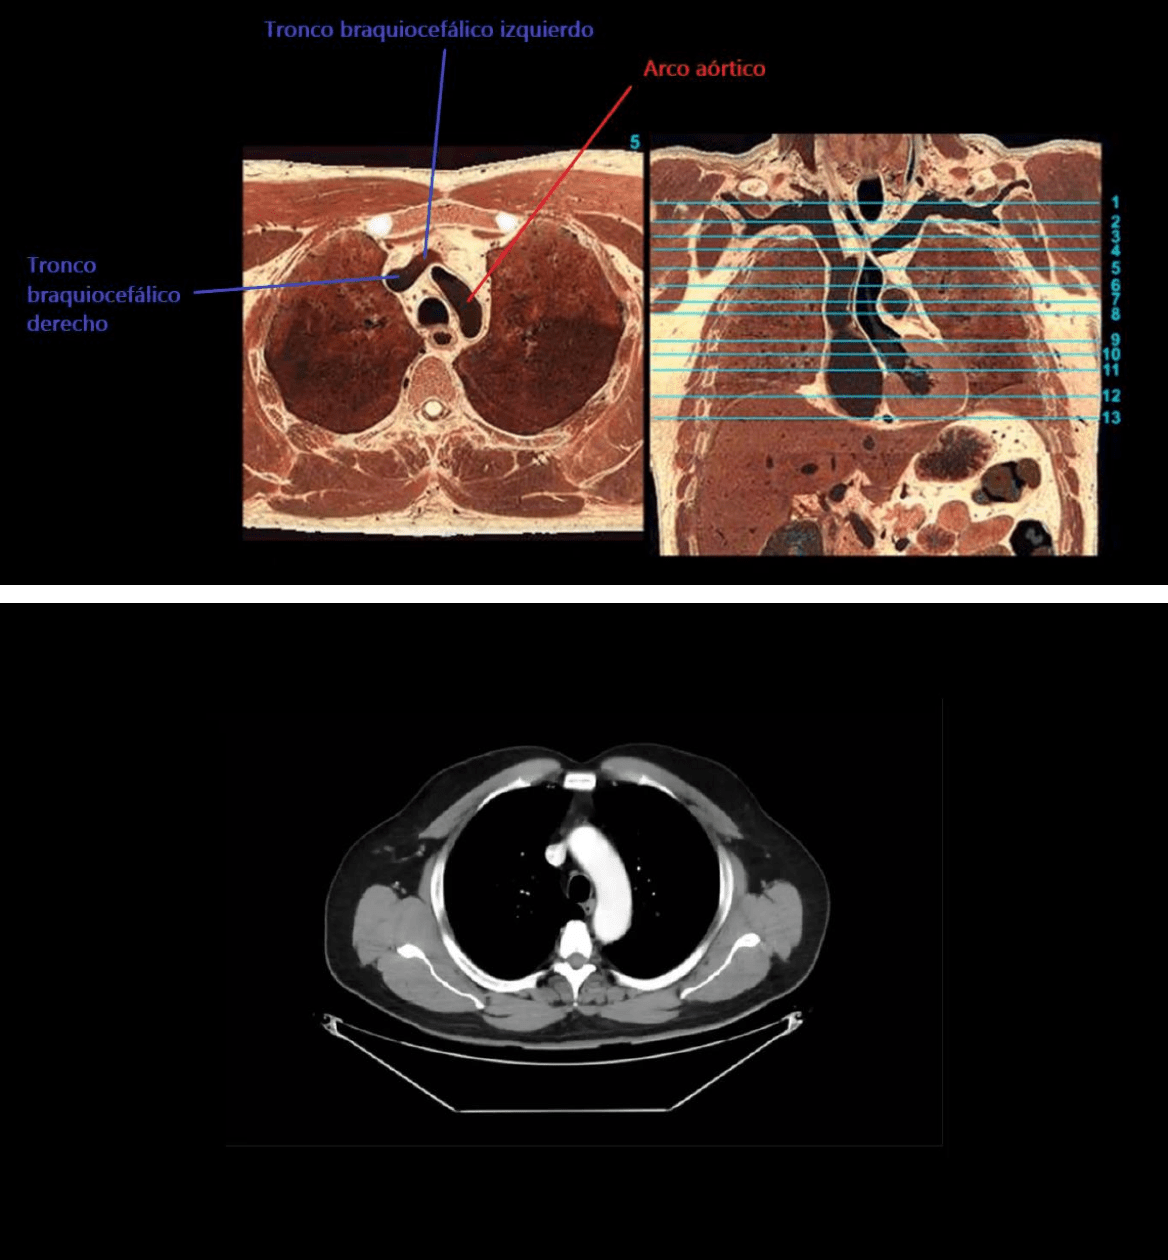

En la radiografía de incidencia de perfil también se ven estructuras mediastinales que están en contacto con parte del

parénquima pulmonar aireado.

No hay que olvidar que ciertos sectores deben observarse radiolúcidos (zonas aireadas) en la incidencia de perfil, si no se

observan de esa forma, indican cierto tipo de patologías:

1.- ESPACIO RETROESTERNAL: Patologías donde se ve radioopaco, agrandamiento de aorta ascendente, agrandamiento

del timo, agrandamiento de glándula tiroides.

2.- ESPACIO RETROCARDÍACO.

3.- ESPACIO RETROTRAQUEAL.